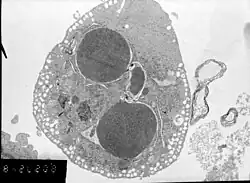

Neonatal cardiomyocytes ultrastructure after anoxia-reoxygenation